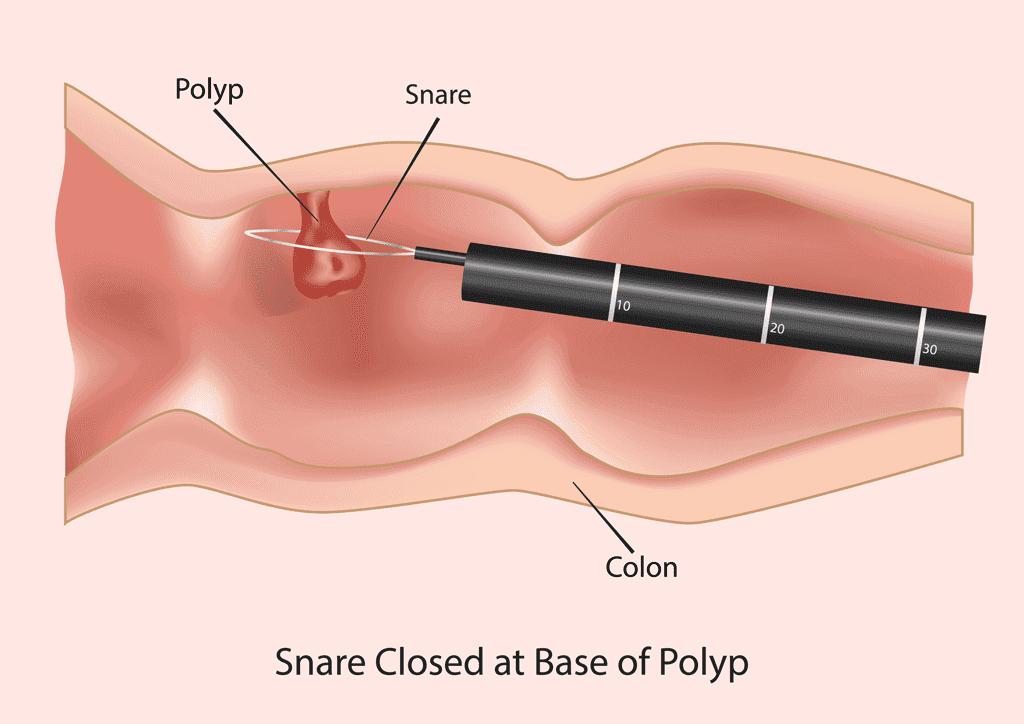

ESD/EMR (Endoskopik Submukozal Diseksiyon/Mukozal Rezeksiyon)

Erken evre gastrointestinal tümörlerin cerrahi olmadan endoskopik yöntemle çıkarılması.

- ✓Erken evre mide ve kolon kanserlerinin tedavisi

- ✓Büyük poliplerin tek parça halinde çıkarılması

- ✓Barrett özofagus tedavisi

- ✓Minimal invaziv yaklaşım